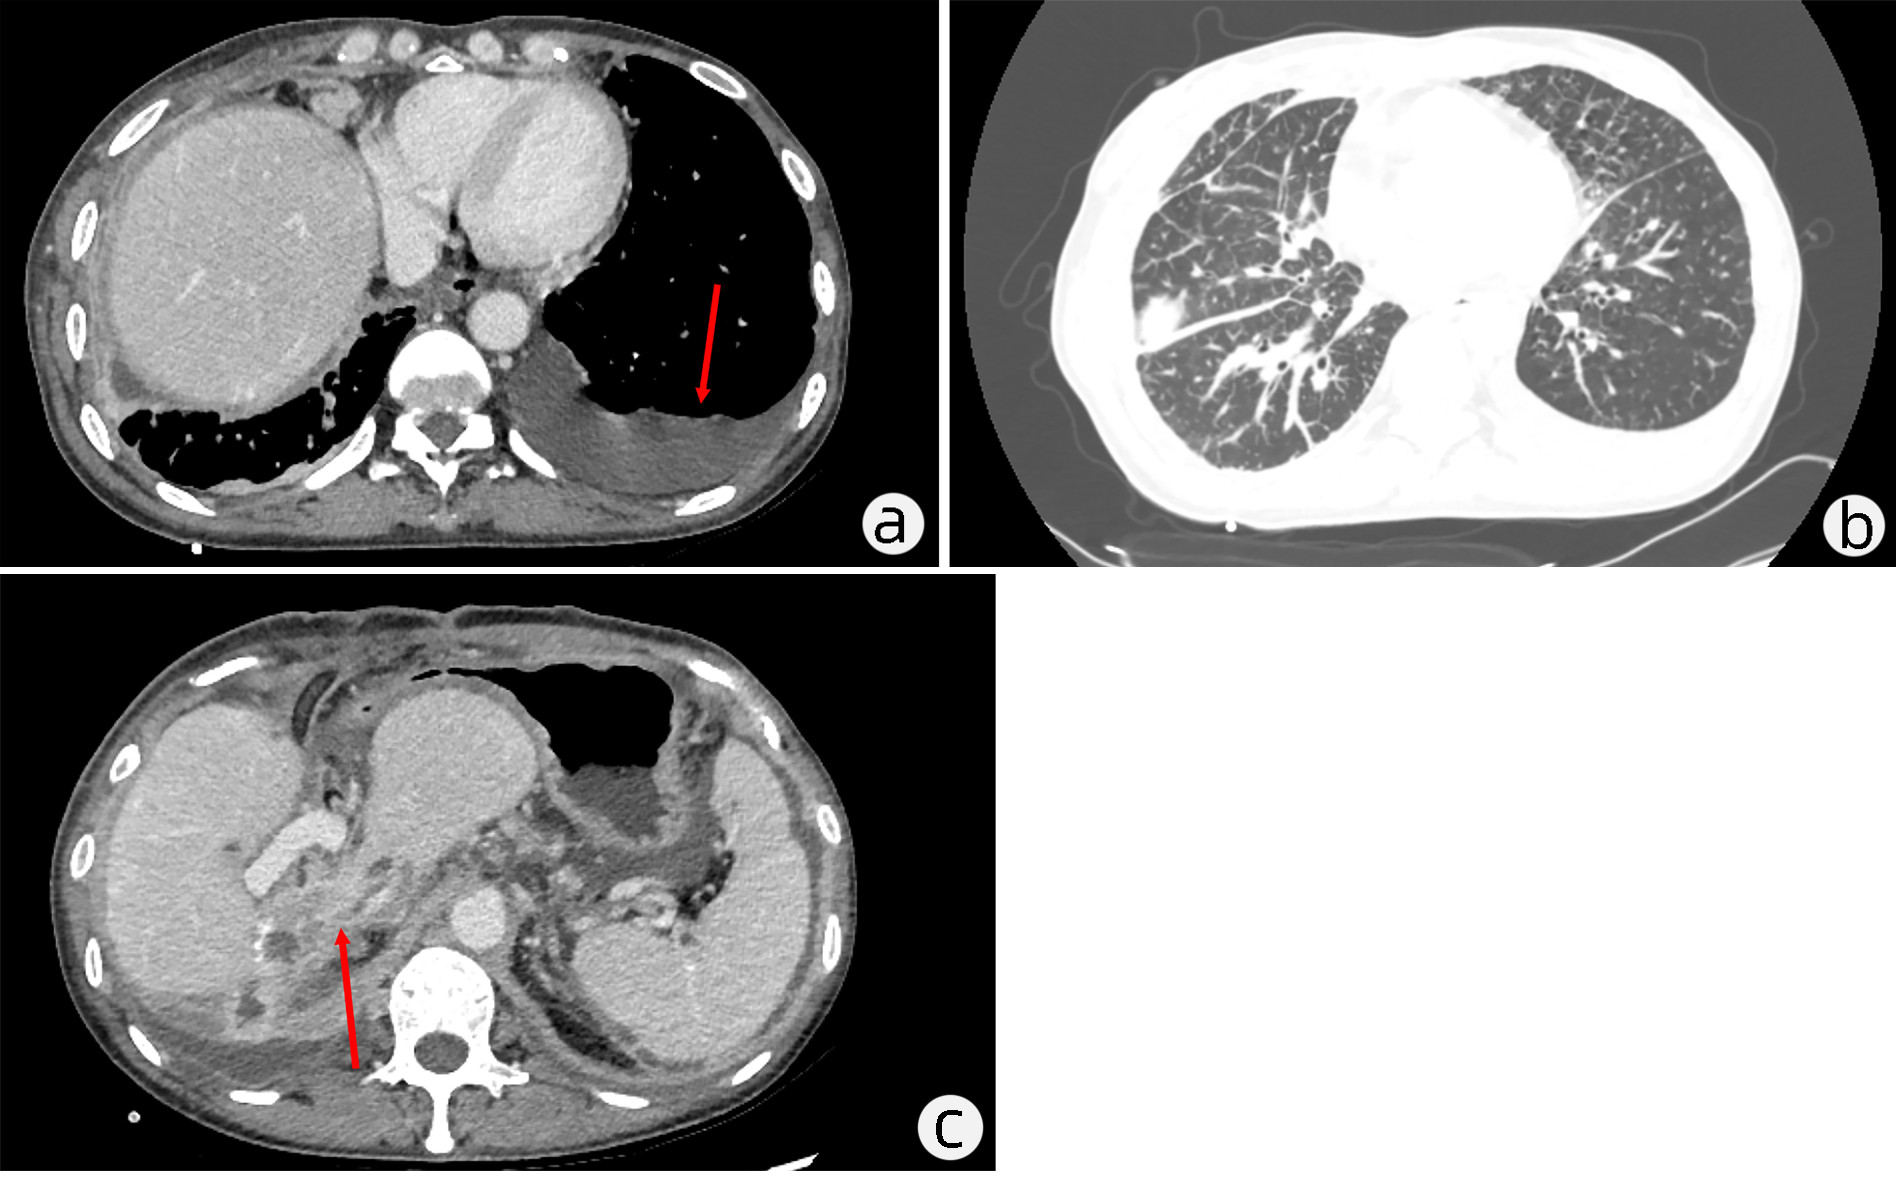

A case of chronic gelatinous ascites caused by giant intraductal papillary mucinous neoplasm of the bile tract

Congying CHEN, Ruling ZHANG, Liang QIAO, Lungen LU, Hui ZHOU

2023, 39(1): 147-151. DOI: 10.3969/j.issn.1001-5256.2023.01.022

Abstract(2426) HTML (1406) PDF (2992KB)(126)

Abstract: